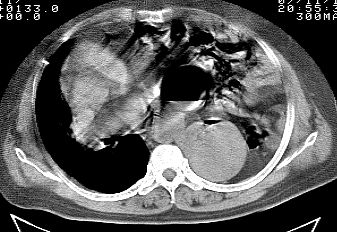

标题: CT10753:女, 64岁 隔疝 [打印本页]

标题: CT10753:女, 64岁 隔疝

女, 64岁 三十年前胸部外伤史, 间断胸闷,

典型左侧膈疝,疝出物为胃和大网膜,纵隔右移

同意左侧膈疝,不过,有过外伤史,左肺有受压征象,同时有胸膜增厚。